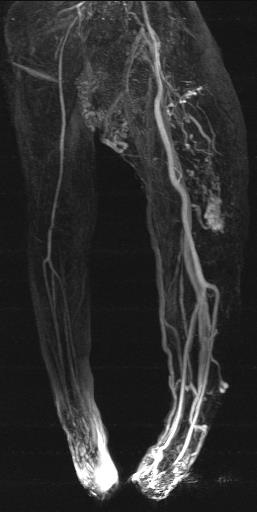

♀, 3 ys, Parkes-Weber-Syndrom. Therapeutic goal: healing & socialisation